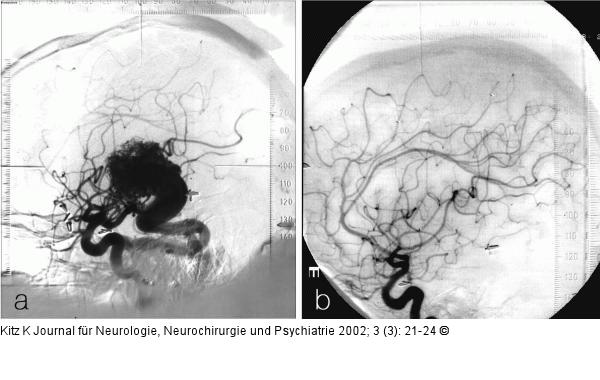

Abbildung 5a-b: AV-Malformation - Planung für Gamma Knife 5a: AVM im Thalamus re, St. p. Blutung, St. p. Teilexstirpation, Gamma Knife-Planungsangiographie (A. carotis interna re). 5b: Kontrollangiographie (A. carotis interna re.) nach 36 Monaten, komplette Obliteration der AV-Malformation |

5a: AVM im Thalamus re, St. p. Blutung, St. p. Teilexstirpation, Gamma Knife-Planungsangiographie (A. carotis interna re). 5b: Kontrollangiographie (A. carotis interna re.) nach 36 Monaten, komplette Obliteration der AV-Malformation |